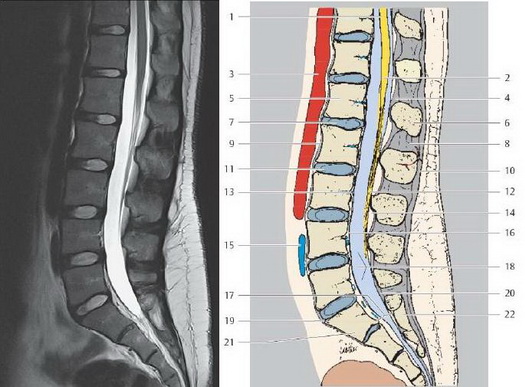

МРТ поясничного отдела позвоночника

1. Спинной мозг

2. Мозговой конус

3. Абдоминальная аорта

4. Желтая связка

5. Тело поясничного позвонка L1

6. Остистый отросток L1

7. Межпозвоночный диск L1/L2 (студенистое ядро)

8. Межостистая связка

9. Передняя продольная связка

10. Надостистая связка

11. Межпозвоночный диск L2/L3

12. Конский хвост

13. Базально-позвоночная вена

14. Эпидуральная жировая клетчатка

15. Левая общая подвздошная вена

16. Задняя продольная связка

17. Крестцовый канал

18. Текальная сумка (поясничная цистерна)

19. Мыс крестца

20. Твердая мозговая оболочка

21. Крестец (S1)

22. Медиальный крестцовый гребень

1. Диафрагма (поясничная часть)

2. Пояснично-грудная фасция

3. Переднее наружное позвоночное венозное сплетение

4. Мышца, выпрямляющая туловище

5. Задняя межреберная артерия

6. Нервные волокна

7. Тело грудного позвонка

8. Верхний суставной отросток

9. Тело поясничного позвонка L1

10. Задняя дуга позвонка (пластина)

11. Межпозвоночный диск L1/L2

12. Желтая связка

13. Нижняя полая вена

14. Переднее внутренне позвоночное венозное сплетение

15. Межпозвоночный диск L2/L3

16. Поясничная артерия и нерв

17. Поясничная артерия

18. Многораздельная мышца

19. Общая подвздошная артерия

20. Крестец (S1)

21. Спинномозговой узел

23. Мыс крестца

МРТ позвоночника на сегодняшний день основной метод выбора в диагностике грыж межпозвонковых дисков, являющихся наиболее частой причиной болей в позвоночнике (до 80%), а также других дегенеративно-дистрофических заболеваний позвоночника, воспалительных и опухолевых изменений позвонков, мягких тканей и структур спинного мозга.